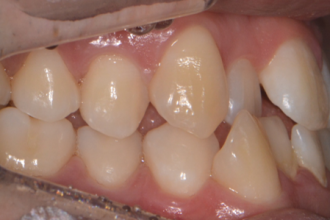

치아교정

굿프렌즈 치과 임상 케이스